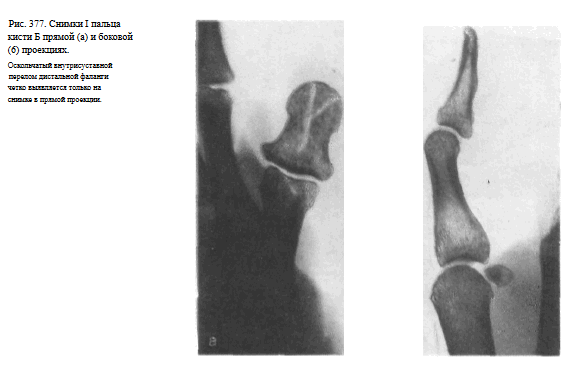

На рентгенограмме видны фаланги и частично I пястная кость, их медиальные и латеральные поверхности, рентгеновские суставные щели пястно-фалангового и межфалангового суставов, бугристость дистальной фаланги (рис. 374).

Снимок I пальца в боковой проекции. I палец прилежит к кассете лучвым (наружным) краем.

Остальные пальцы слегка согнуты, опираются концами на перекрытую листом просвинцованно резины уже проэкспонированную половину кассеты.

Пучок рентгеновского излучения направлен на проекцию пястно-фалангового сустава (рис. 375).

На рентгенограмме выявляются тыльная и ладонная поверхности фаланг и частично I пястной кости.

Видны наслаивающиеся друг на друга сесамовидные кости рядом с головкой I пястной кости (рис. 376). Снимки необходимо выполнять в двух взаимно перпендикулярных проекциях (рис. 377, а, б).